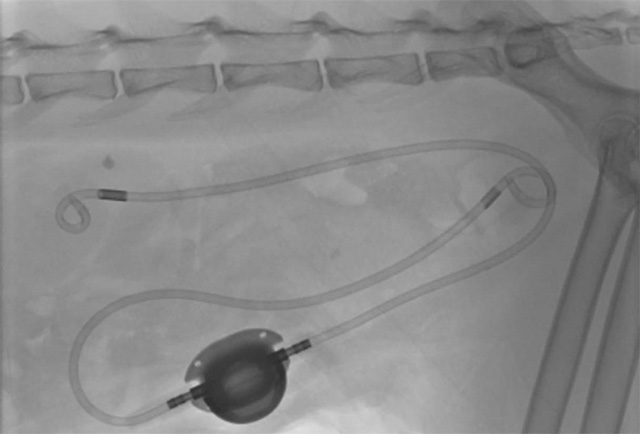

尿の通り道に石ができる病気です。当院では石を溶かす内科療法だけでなく、外科手術にも幅広く対応。特に、難易度の高い「SUBシステム(人工尿管設置術)」などの特殊なステント手術も実施可能であり、他院で処置が難しいと言われた症例もご相談いただけます。

猫ちゃんの尿管結石は命に関わる重篤な事態を招きます。当院ではマイクロサージェリー(微細外科)を用いた繊細な手術実績が豊富にあり、小さな体への負担を最小限に抑えた治療を行います。

尿管結石や膀胱腫瘍など、高度な技術を要する外科手術を数多く執刀しています。特に、SUBシステム(人工尿管設置術)に対応している点は、宝塚・伊丹エリアにおいても大きな強みです。